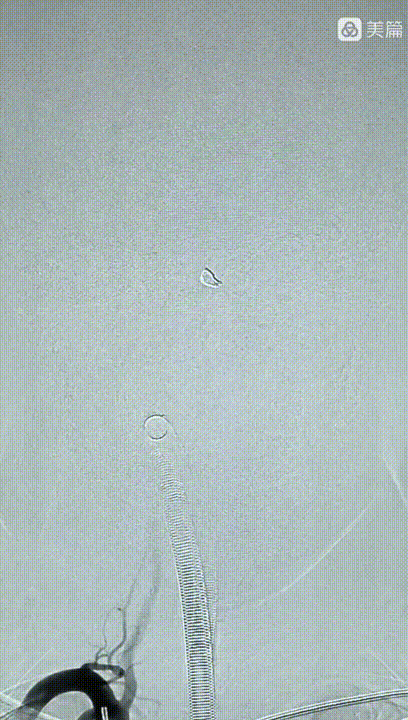

继续填塞弹簧圈,瘤体近端约2mm的血管一并栓塞做成“塞子”。

数枚弹簧圈进去,载瘤动脉及动脉瘤致密栓塞,小脑后下动脉显影良好,且有侧支与基底动脉近端联通。